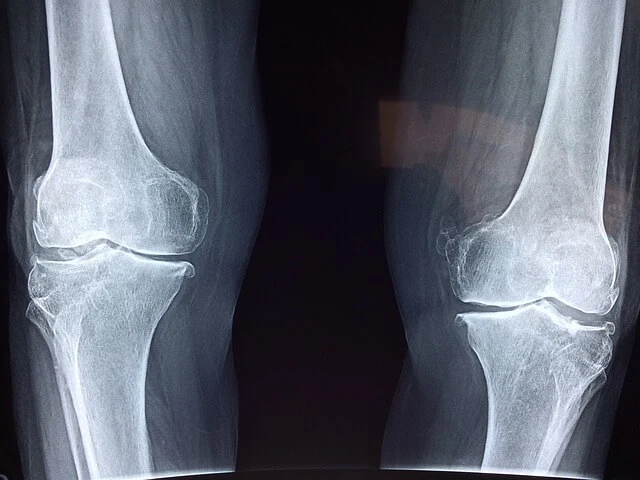

📌 (대상질환) 건강보험급여 '인공관절치환술(슬관절)' 인정기준에 준하는 질환자

무릎관절염은 무릎 관절 안의 관절 연골이 점차 사라지고, 관절을 이루는 뼈와 관절막, 주변 인대 등에 손상과 염증이 동반되는 질환입니다. 관절 주변에 통증과 변형이 일어나 기능에 장애가